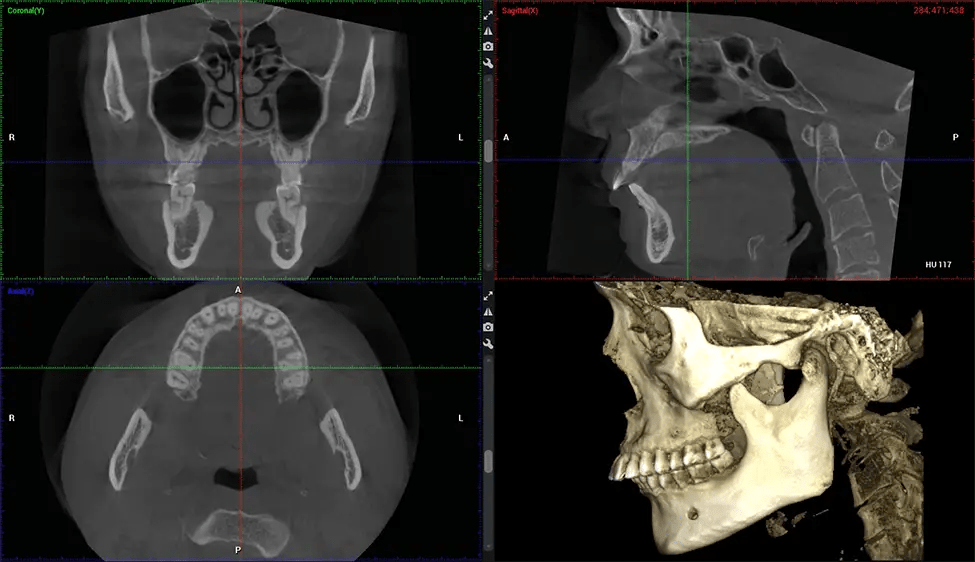

Cráneo completo hasta C7 de la columna vertebral

Planmeca Viso G7 CBCT (Cone Beam CT Scan) está diseñado para superar las demandas de los líderes de la industria, los especialistas y las grandes instituciones. Tiene un gran sensor de ø25×30 cm con cuatro cámaras integradas. Puede capturar tamaños de volumen ilimitados, desde ø3×3 cm hasta ø30x30cm, capturando el casquete escutelario a través de C7 en la columna cervical. Planmeca Viso G7 ofrece el escaneo de volumen único más grande de la industria de ø30×19 cm. Está preparado para manejar modalidades de imágenes avanzadas como la tecnología Planmeca ProFace® y Planmeca 4D™ Jaw Motion. El soporte occipital para la cabeza permite una visión sin obstáculos del tejido facial.